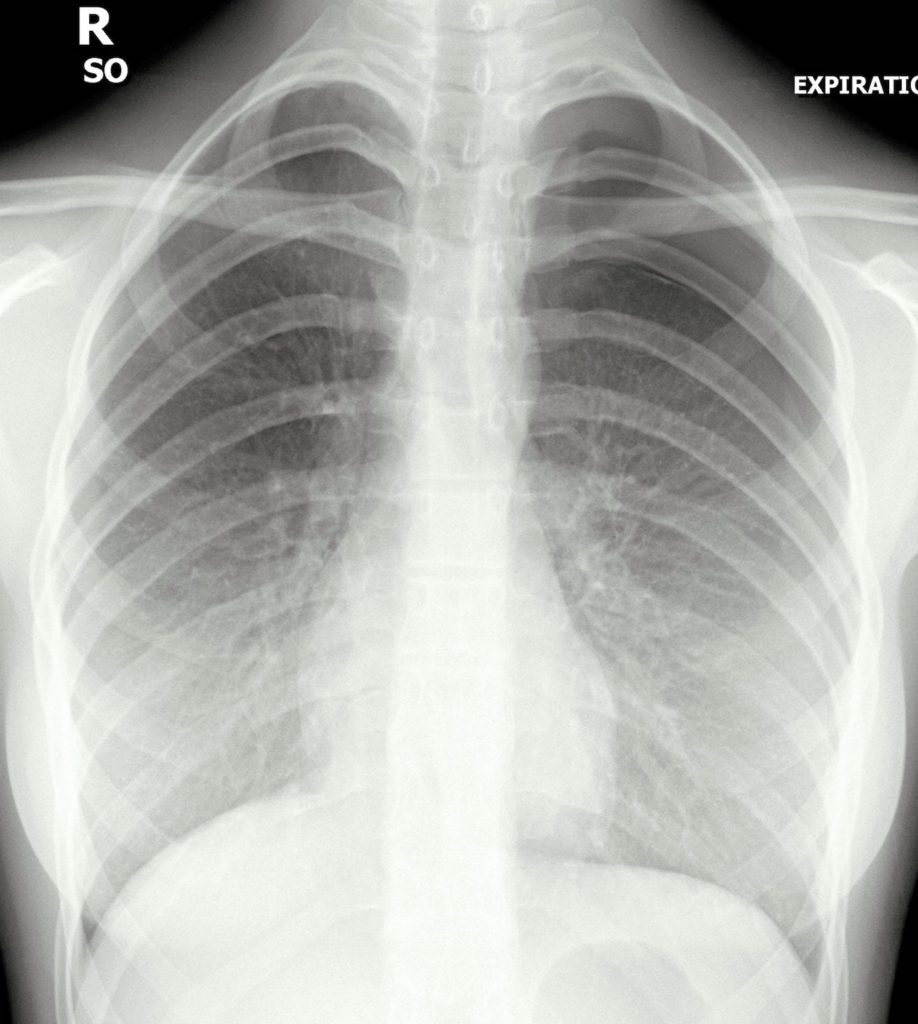

Chest Xray Historyright Pleuritic Chest Pain Stock Photo 1616553016 What Is Chest Pain Pleuritic Details of your symptoms, including where your chest pain starts and how far it spreads. Each pleura consists of two thin,. A pleuritic pain is a chest pain which is typically sharp and 'stabbing' in a part of the chest. The pain is usually made worse when you breathe. Pleurisy is an inflammation of the lining of your lungs (pleura). What Is Chest Pain Pleuritic.

Pleurisy In Chest XRay Various Radiographs To Show And Depict This What Is Chest Pain Pleuritic Details of your symptoms, including where your chest pain starts and how far it spreads. What are the signs and symptoms of pleurisy? The pain is usually made worse when you breathe. When a person has pleurisy, a doctor will look for the underlying cause of the inflammation. In some cases, a person can also. A pleuritic pain is a. What Is Chest Pain Pleuritic.